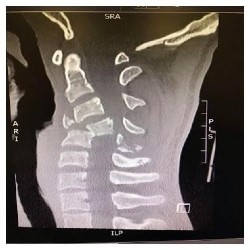

Fracture de Jefferson au niveau de l’arc antérieur C1 (première vertèbre) et élargissement du canal rachidien secondaire à la fracture de l’arc antérieur de C1.

Les radiographies peuvent détecter plusieurs fractures cervicales, telle que la fracture de Jefferson au niveau de la deuxième vertèbre. Ce type de fracture crée une ouverture de l’anneau de la première vertèbre et, en conséquence, un élargissement du canal rachidien (conduit à l’intérieur de la moelle épinière). Il est possible de voir une entorse grave des deux premières vertèbres. Ce trauma est souvent lié à une hyperflexion du cou, ce qui donne lieu à une lésion du ligament transverse empêchant un frein postérieur. Une partie de la première vertèbre cervicale se déplace alors vers l’arrière et comprime le canal spinal. Il est donc possible de voir, sur une radio de profil, le déplacement de l’arc antérieur de C1 et la face antérieure de l’odontoïde.

Fractures multiples de la colonne cervicale et compression médullaire (déformation de la moelle épinière) (coupe sagittale).